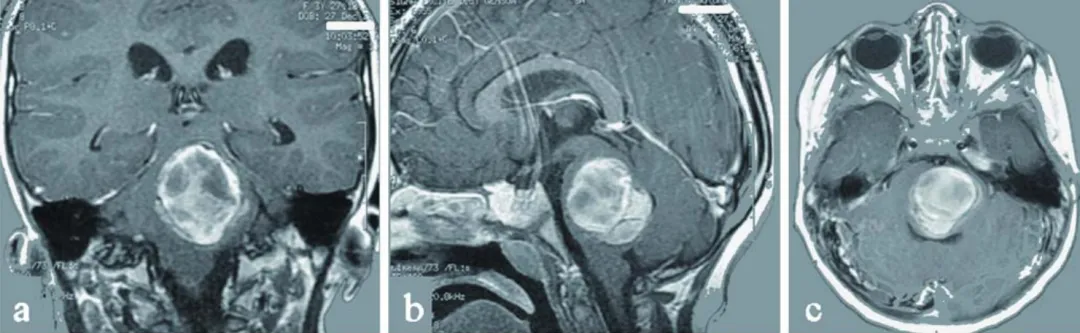

3岁女童阿莉莎突发剧烈头痛伴呕吐症状,起病无明显前兆。病情呈进行性加重,右侧肢体活动功能逐渐丧失,伴随面部不对称表现。经影像学检查,MRI结果显示脑桥区存在4×3×5厘米巨大海绵状血管瘤伴出血征象,颅内可见多发病灶。

磁共振成像(MRI)检查明确显示:脑桥区域存在4×3×5厘米巨大海绵状血管瘤,同时颅内发现多个附加病灶。其中左侧额叶病灶已引发癫痫发作,需药物控制。病因明确为脑桥病灶增大合并出血,持续压迫关键神经中枢结构。

图a-c为术前影像学资料